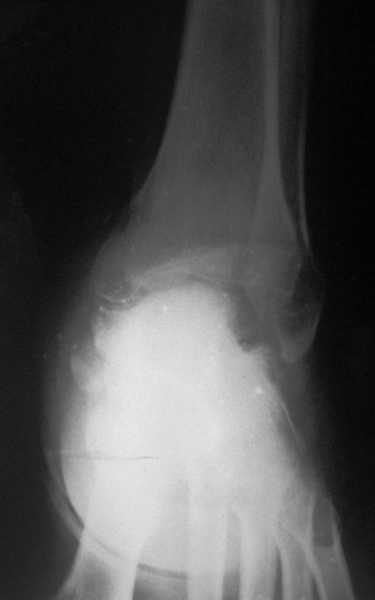

Глубокоуважаемые коллеги! Просим совета в лечении пациента с последствиями тяжелой сочетанной травмы. Пациент С., 41 года, по профессии бизнесмен, в сентябре 2005 г. пострадал в дорожно-транспортном происшествии (упал с мотоцикла). Диагноз: ЗЧМТ, ушиб головного мозга тяжелой степени. Открытый переломо-вывих левой таранной кости. Закрытые переломы лонной и седалищной костей слева. Был доставлен в НИИСП им. Н.В. Склифосовского. При ПХО раны выявлен открытый перелом левой таранной кости (III тип по Hawkins) с утратой вывихнутого тела таранной кости. Выполнена ПХО, фиксация голени и стопы стержневым аппаратом. Рана зажила без осложнений. Аппарат демонтирован через 1,5 месяца. В настоящее время больной предъявляет жалобы на боль в голеностопном суставе при нагрузке. Передвигается с опорой на костыли с дозированной нагрузкой на левую стопу.Голень и стопа фиксированы циркулярной пластиковой повязкой. Сохраняются остаточные явления ЧМТ (в виде сниженной критики к своему состоянию и определенной недисциплинированности в выполнении врачебных рекомендаций) Рентгенограммы – рис. 1, 2 (просим извинения за низкое качество рентгенограмм), схема – рис. 3. В качестве варианта хирургического лечения мы считаем возможным выполнить следующее вмешательство: артродез большеберцовой и пяточной костей в сочетании с артродезом переднего края большеберцовой кости и головки таранной кости с фиксацией спонгиозными винтами. Считаем выполнение артродеза переднего края большеберцовой кости и элементов I луча стопы необходимым для максимального восстановления опороспособности конечности. Однако выполнение операции в указанном объеме привело бы к относительному укорочению внутреннего свода стопы. Мы видим два пути решения данной проблемы: Вариант 1. Применение костного трансплантата (свободного или на сосудистой ножке) для замещения дефекта головки таранной кости и сохранения геометрии внутреннего свода стопы (рис 4). Преимущество: относительная простота операции. Недостаток: высокий риск замедленной консолидации или лизиса трансплантата. Вариант 2. Резекция участка пяточной кости с последующим остеосинтезом винтами для укорочения наружного свода стопы (рис 5, 6). Преимущества: сохранение собственного кровоснабжения всех синтезируемых участков костей. Недостатки: дополнительная травматизация, усугубление деформации стопы в виде нарушения наружного свода. Будем признательны за ваши предложения, включая возможные альтернативные варианты лечения.Заранее благодарны за добрые советы и поддержку. А. Федосов, О. Диденко, П. Иванов. Отделение множественной и сочетанной травмы НИИСП им. Н.В. Склифосовского, г. Москва.

Ваша дискуссия заставила перелистать свои наблюдения.

Среди повреждений таранной кости (Hawkins III-IV) с одновременной травмой лодыжек встретилось следующее (см. вложение). Пациент упал в колодец на глубину 10 метров (Х.2002 г.), госпитализирован с диагнозом: з/перелом шейки правой таранной кости (Hawkins IV) с переломовывихом тела назад и кнутри, закрытый перелом внутренней лодыжки и переднего края большеберцовой кости. Оперирован в первые 12 часов после травмы, выполнена открытая репозиция таранной кости, внутренним и передне-внутренними доступами, остеосинтез переломов шейки и тела губчатыми винтами, для реваскуляризации тела таранной кости первичный компрессионный над- и подтаранный артродез. Синтез внутренней лодыжки губчатым винтом. Удаление винтов через 1 год,2 мес. Получен анкилоз указанных суставов с сохранением длины конечности, полная реваскуляризация таранной кости, о чем говорит сращение ее переломов, отсутствие отеков и

цианоза стопы и голени. Компенсаторная подвижность переднего и среднего отделов стопы около 15-20 градусов за счет поперечного (Шопара) сустава стопы. Считаю оправданной подобную тактику, не смотря на угрожаемый прогноз (100% асептический некроз) по классифицкации Hawkins.